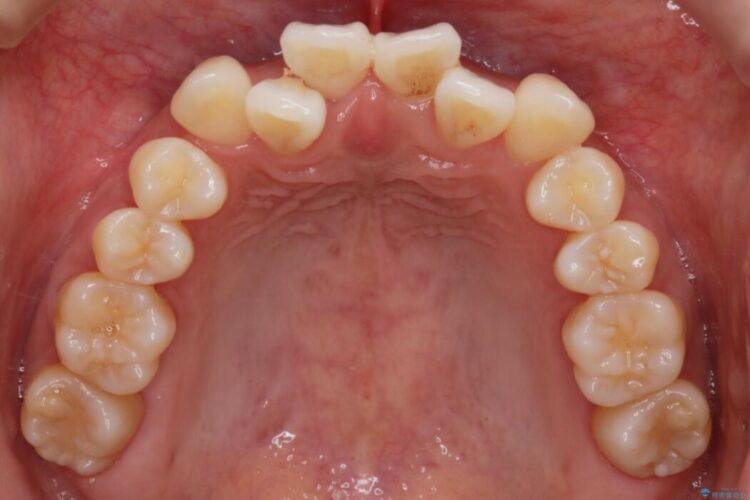

検査の結果、骨の厚みに余裕がないことが判明しましたので、幅の拡大と歯の側面を削るIPRでは歯周病に対する不安を拭いきれないと判断しました。

よってマイクロインプラントを用い、奥歯から順番に遠心移動させることによってスペースを確保することにしました。

歯の遠心移動

歯を後方に移動させてスペースを確保する場合、マウスピースの装着時間に加えて装着時の適合度が良い状態に保たれているかが鍵となります。